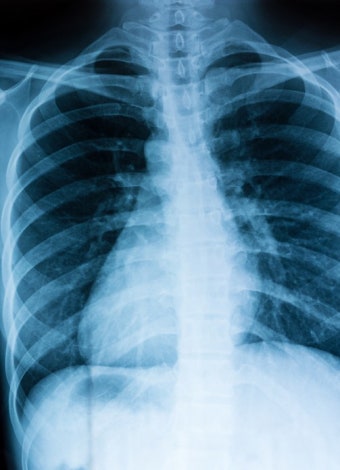

전문의의 X-ray 또는 CT 진단을 통해 결정됩니다.